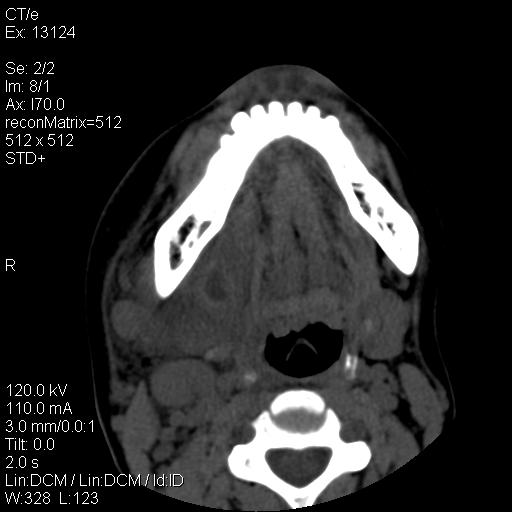

标题: CT18257:女,29岁,右下磨牙痛 [打印本页]

标题: CT18257:女,29岁,右下磨牙痛

女,29岁,右下磨牙痛,因产后2月,故未治疗。现右颌肿痛伴张口困难。请大家看看右侧鼻咽部、口咽部是否

1.考虑右侧下颌区脓肿(牙源性)

2.右侧上颌窦炎症、两侧下鼻甲肿大

1)考虑右侧下颌区软组织脓肿(牙源性)。2)鼻咽部炎性改变;建议追踪复查。3)右侧上颌窦炎。4)双侧下鼻甲黏膜肥厚。

1)考虑右侧下颌区牙源性软组织脓肿。2)右侧上颌窦炎。3)双侧下鼻甲黏膜肥厚。4)鼻咽部炎性改变;建议追踪复查。